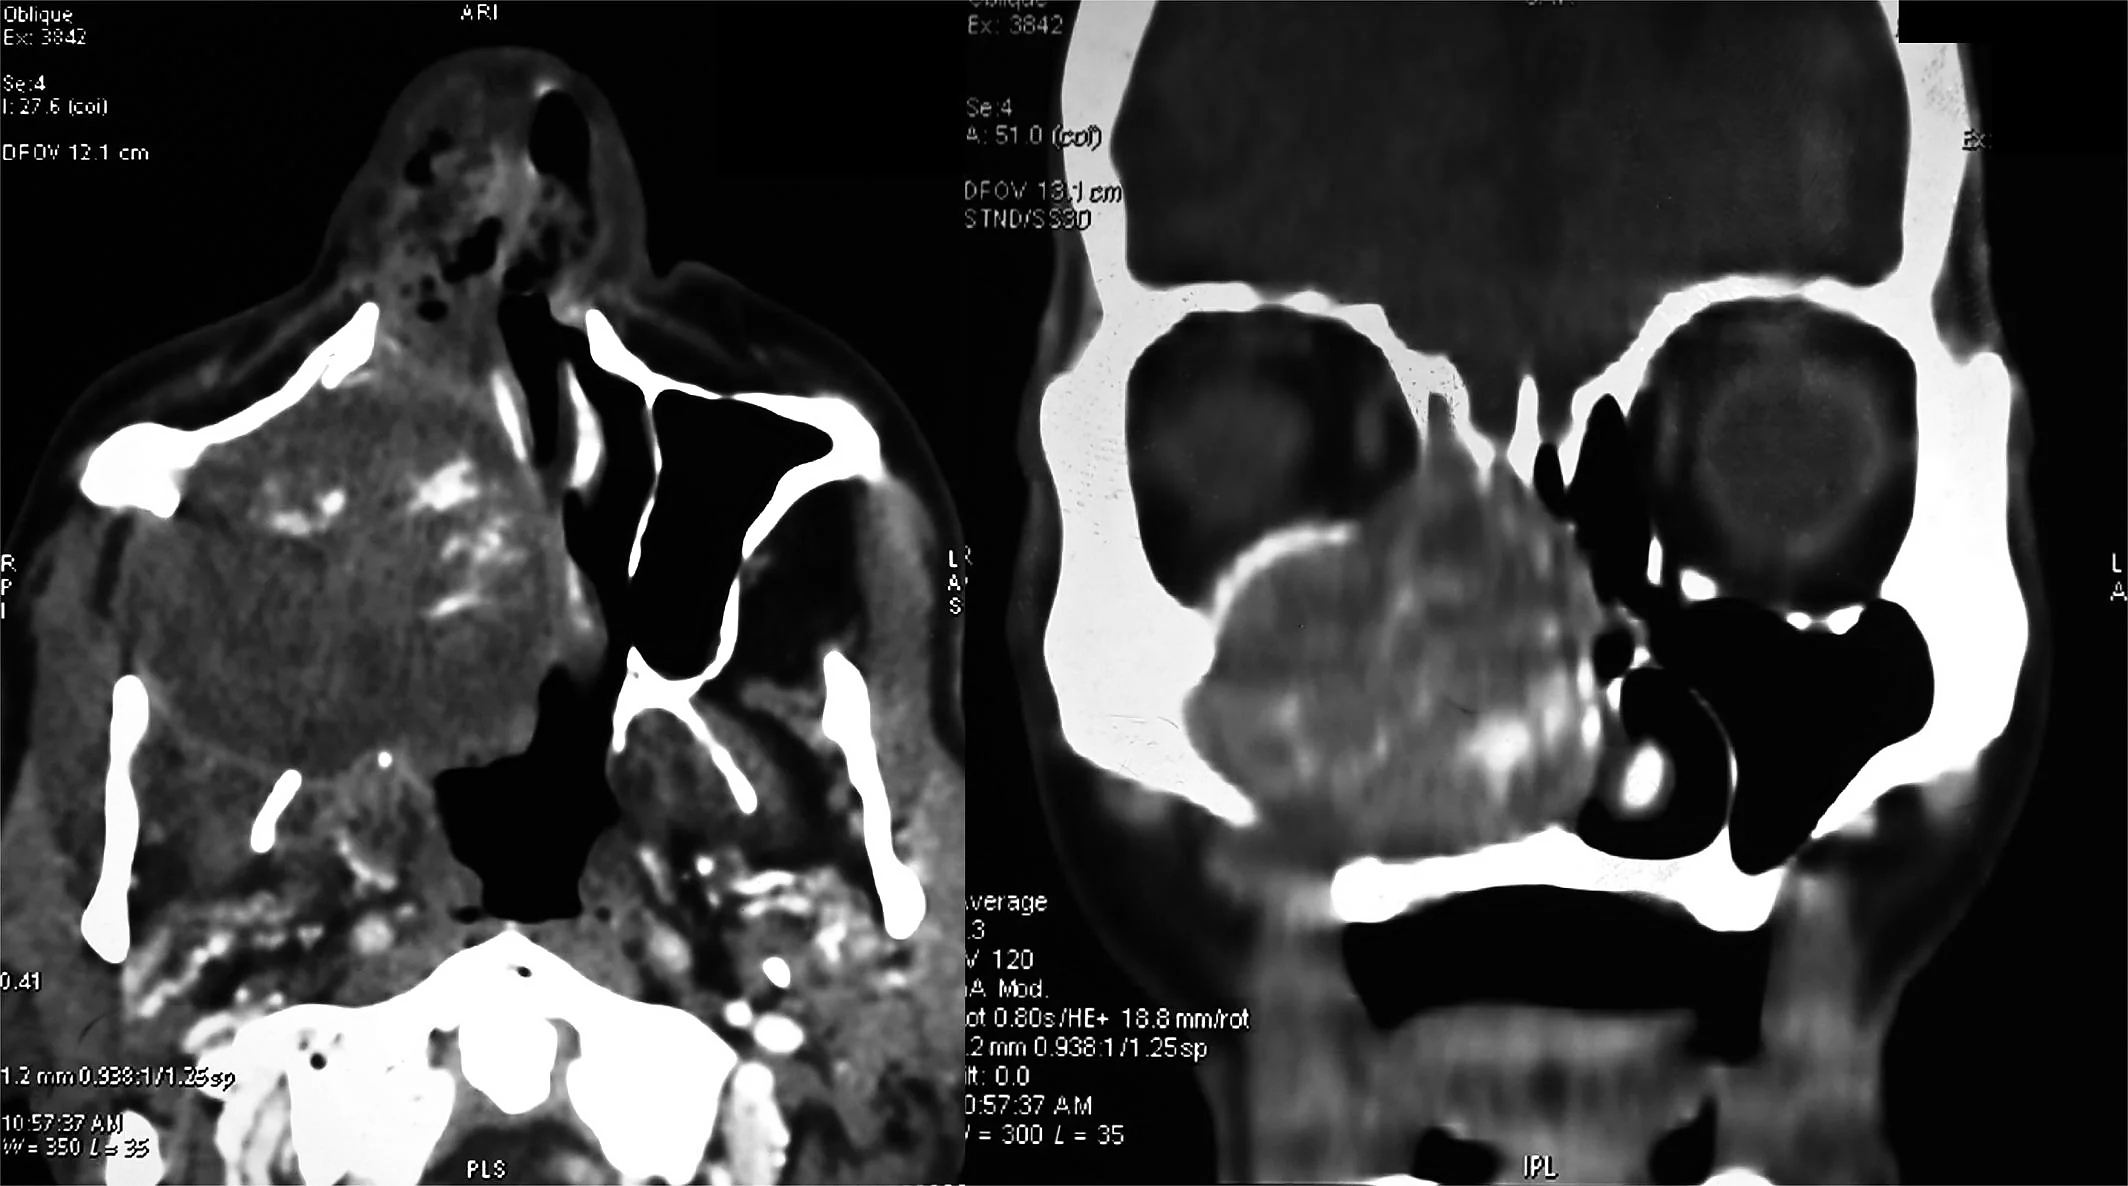

An “enormous” gossypiboma, which is a mass inside the body composed of retained surgical gauze or sponge surrounded by an inflammatory foreign body reaction.